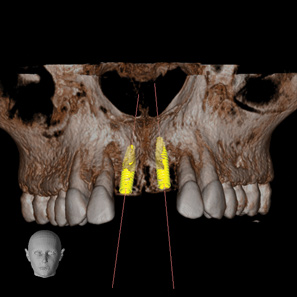

Fig 3. CBCT images show axial (Fig 2) and cross-sectional (Fig 3) views, and 3D reconstruction view (Fig 4) with virtually planned implant Nos. 8 and 9.

Figure 3

Fig 4. CBCT images show axial (Fig 2) and cross-sectional (Fig 3) views, and 3D reconstruction view (Fig 4) with virtually planned implant Nos. 8 and 9.

Figure 4

Fig 2. CBCT images show axial (Fig 2) and cross-sectional (Fig 3) views, and 3D reconstruction view (Fig 4) with virtually planned implant Nos. 8 and 9.

Figure 2

For dental implant-based treatment, the planning phase begins with collection of basic data sets; this is digital touchpoint 1. It includes: (1) a cone-beam CT (CBCT) to view edentulous areas or failing tooth structure, bone, and anatomic landmarks under the soft tissue (Figure 2 through Figure 4); and (2) an intraoral optical scan (IOS) or a scanned model or impression to record the soft tissue and tooth anatomy (Figure 5). The superimposition of the digital imaging and communications in medicine (DICOM) files from the CBCT and the standard tessellation language (STL) files from the IOS allows visualization of how bone, dental structures, and soft tissues relate. Both digital data points are key to implant selection and determining the surrounding bone-grafting needs. An initial treatment plan includes determining the desired implant manufacturer/implant design, size, and positions; these decisions remain the responsibility of the dentist (restoring and surgical team members) and not the technician or planning team.